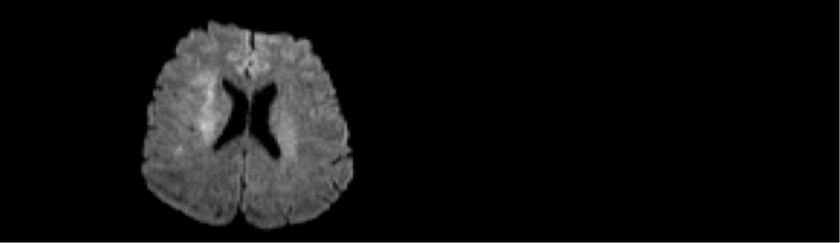

Diffusion:

Im Versorgungsgebiet der rechten A.cerebri media stellt sich ein beginnend diffusionspositives Areal dar (Pfeil).